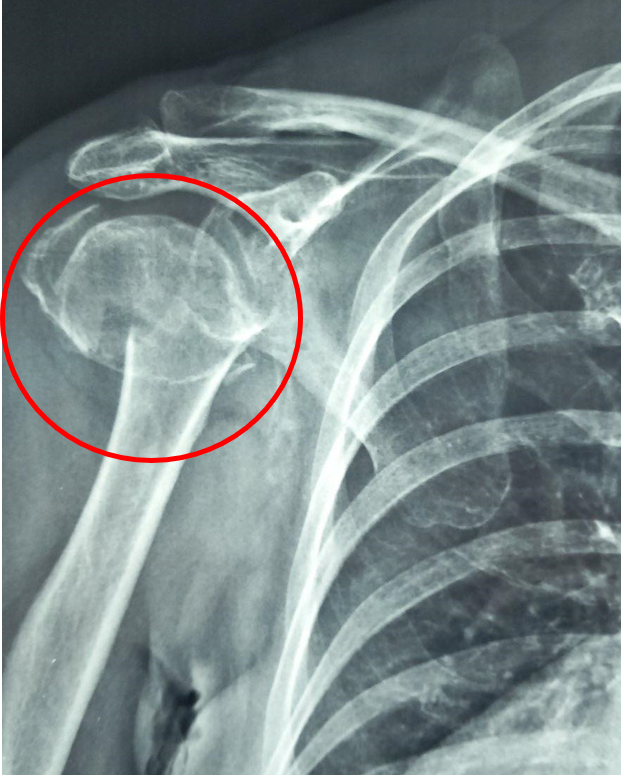

Κάταγμα Κεφαλής Βραχιονίου

Τι Είναι;

Το κάταγμα κεφαλής βραχιονίου αποτελεί μια μορφή κατάγματος που αφορά την περιοχή του ώμου και συγκεκριμένα το εγγύς τμήμα του βραχιονίου οστού. Τα κατάγματα της κεφαλής χρήζουν ιδιαίτερης προσοχής και μπορεί να είναι ιδιαίτερα απαιτητικά στην αντιμετώπισή τους. Αυτό οφείλεται στην περίπλοκη ανατομία της περιοχής που περιλαμβάνει μεταξύ

άλλων και τους μύες και τένοντες του στροφικού πετάλου, οι οποίοι είναι υπεύθυνοι για τις κινήσεις και την σταθερότητα του ώμου. Εφόσον το κάταγμα της κεφαλής του βραχιονίου δεν αντιμετωπιστεί σωστά μπορεί να επηρεαστεί η συνολική σταθερότητα και λειτουργικότητα της άρθρωσης του ώμου.

Διάγνωση

Ο ασθενής με κάταγμα κεφαλής του βραχιονίου χρειάζεται εκτίμηση από εξειδικευμένο Ορθοπαιδικό Χειρουργό. Ο κ. Βλάχος αφού σας εξετάσει προσεκτικά και λάβει το ιστορικό σας θα πραγματοποιήσει υπερηχογράφημα με σκοπό να ελέγξει την

ακεραιότητα των τενόντων του στροφικού πετάλου. Επίσης θα χρειαστεί η λήψη μιας ακτινογραφίας για την καλύτερη εκτίμηση του κατάγματος. Σε συγκεκριμένες περιπτώσεις ο ιατρός θα χρειαστεί να σας παραπέμψει για αξονική ή μαγνητική τομογραφία του ώμου.